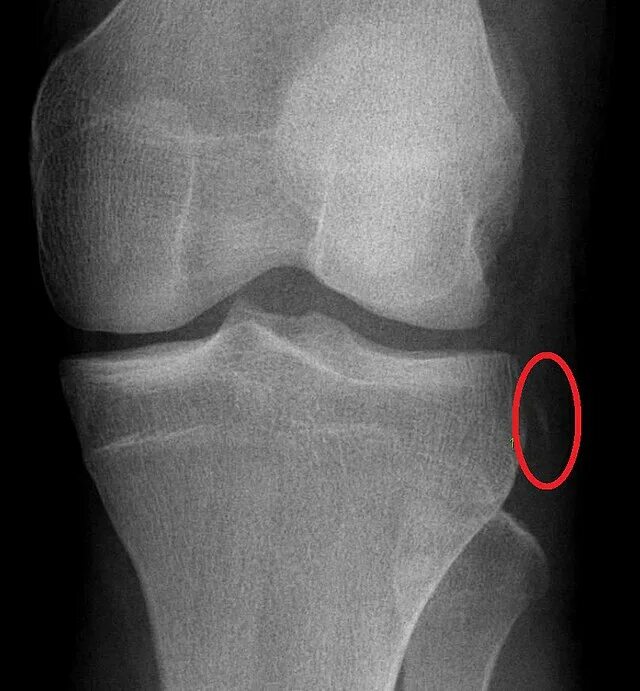

Разрушение мягких тканей